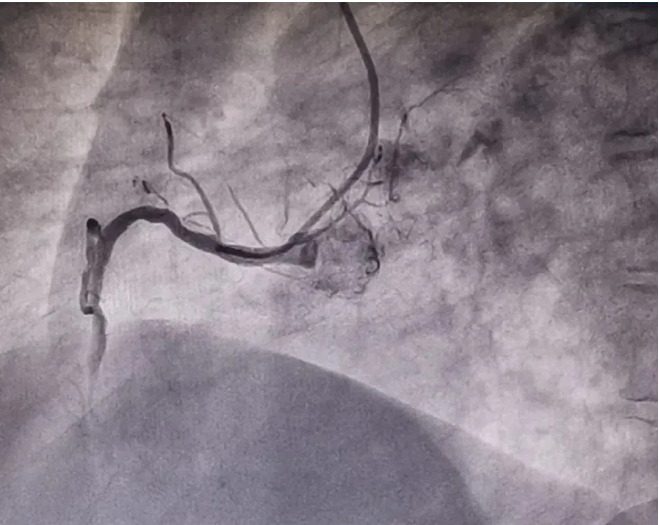

放射科、介入診療室、心血管科與急診科緊急聯(lián)動,迅速會診,制定急性心肌梗死介入治療手術(shù)方案,在冠脈造影檢查過程中發(fā)現(xiàn),患者右冠狀動脈中斷完全閉塞,病情十分危急!李友文主任醫(yī)師迅速將導(dǎo)絲通過閉塞血管,并及時(shí)給予替羅非班血管注入,減輕血小板的聚集,抑制血栓形成,促進(jìn)再灌注形成;球囊通過后給予后適應(yīng)處理,防止再灌注心律失常的發(fā)生。整個(gè)手術(shù)過程順利,成功為患者植入一枚支架,用時(shí)40分鐘,患者術(shù)后恢復(fù)良好。